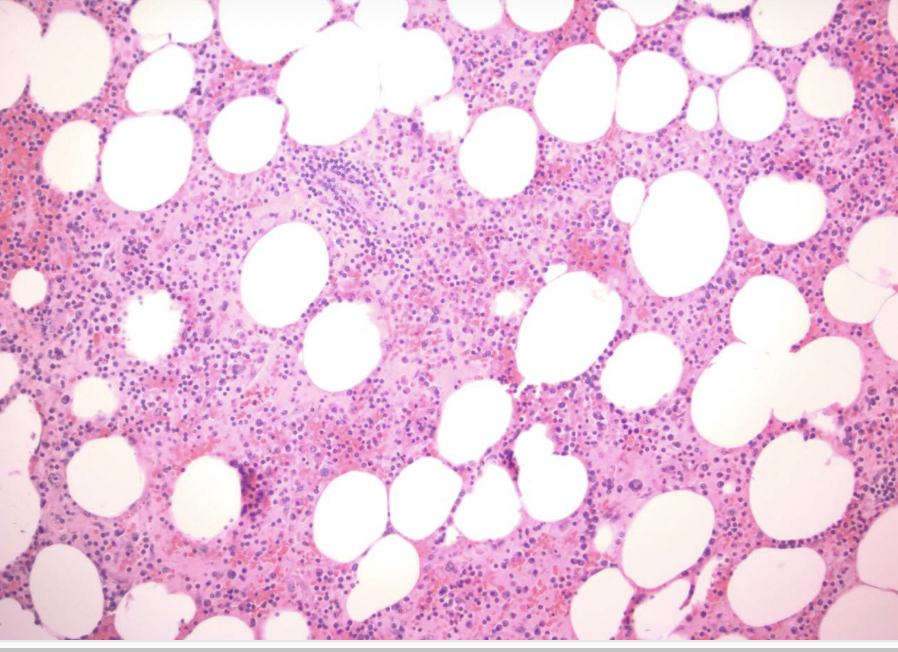

xanthogranulomatous pyelonephritis

sheets of foamy, lipid-laden macrophages

malakoplakia

distinctive chronic inflammatory reaction that appears to stem from acquired defects in phagocyte function

chronic E coli or proteus infection

renal transplant recipients! (immuno comp)

malakoplakia

sheets of large foamy macrophages with granular cytoplasm = von hansemann cells

malakoplakia

michaelis-gutmann bodies = laminated mineralized concretions resulting from deposition of calcium in enlarged lysosomes